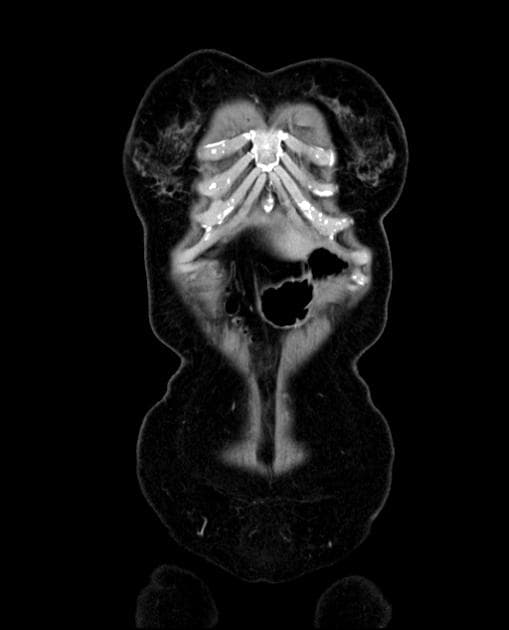

Axial non-contrast

Metastatic hepatoid adenocarcinoma of the stomach

Thành dạ dày dày không đối xứng và tăng quang mạnh do thâm nhiễm u tại tâm vị và phần gần bờ cong nhỏ, kèm theo nhiều hạch bạch huyết lớn quanh dạ dày. Các hạch bạch huyết lớn này tiếp xúc sát với thùy gan trái và tuyến thượng thận trái, cùng với tình trạng tuyến thượng thận trái lớn nhẹ, gợi ý có sự xâm lấn tại chỗ. Có một hạch bạch huyết lớn nằm ở chuỗi hạch dưới hoành phải. Ngoài ra, có một khối lớn, không đồng nhất với bờ không đều ở gan, biểu hiện tăng quang ngoại vi sớm kèm washout muộn và hoại tử trung tâm rộng. Có tình trạng giãn nhẹ ống mật trong gan ở vùng ngoại vi của khối u. Phần còn lại của gan bình thường và không có dấu hiệu của xơ gan nền. Có một nang kích thước 8 mm ở lách. Một vài nang nhỏ cạnh bể thận được ghi nhận ở cả hai thận, quan sát rõ hơn trên các hình ảnh thì bài tiết. Bệnh nhân đã được thực hiện sinh thiết khối u dạ dày qua nội soi và sinh thiết kim lõi khối u gan dưới hướng dẫn siêu âm. Kết quả giải phẫu bệnh và hóa mô miễn dịch xác nhận ung thư biểu mô tuyến dạng tế bào gan nguyên phát của dạ dày kèm di căn gan. THẢO LUẬN: Trường hợp này minh họa một ca ung thư biểu mô tuyến dạng tế bào gan tiến triển ác tính của dạ dày, xuất phát từ tâm vị và phần gần bờ cong nhỏ ở một bệnh nhân lớn tuổi, biểu hiện với di căn hạch vùng tiến triển và di căn gan lớn, nồng độ AFP huyết thanh cao, cùng các đặc điểm hình ảnh có thể rất giống với ung thư biểu mô tế bào gan nguyên phát. Ung thư biểu mô tuyến dạng tế bào gan của dạ dày là một loại ung thư dạ dày hiếm gặp, có độ ác tính cao, về mặt mô học giống với ung thư biểu mô tế bào gan và thường sản sinh alpha-fetoprotein (AFP). Nó chiếm khoảng 1% các trường hợp ung thư dạ dày và thường được phát hiện ở giai đoạn muộn với di căn gan và di căn hạch. Ung thư biểu mô tế bào gan nguyên phát và ung thư biểu mô tuyến dạng tế bào gan của dạ dày di căn gan có thể có hình thái rất giống nhau; tuy nhiên, chúng khác nhau về bối cảnh lâm sàng, đặc điểm hình thái và hóa mô miễn dịch.

Ung thư biểu mô tuyến dạng tế bào gan của dạ dày di căn